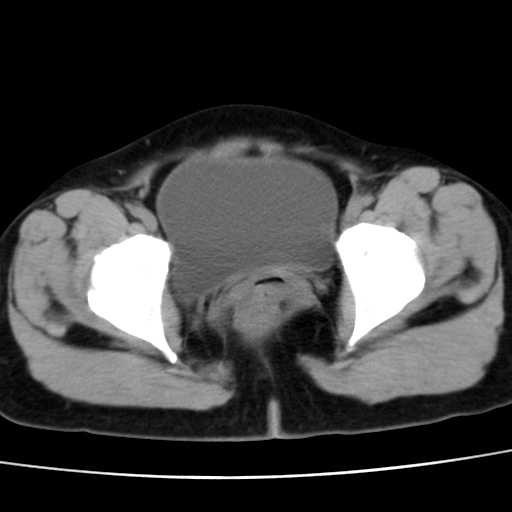

子宫多发肌瘤吗

多发性子宫肌瘤.

考虑多发子宫肌瘤,子宫直肠窝双囊性占位,另直肠周围脂肪密度增高,不知有何病史

支持考虑多发子宫肌瘤~!子宫直肠陷凹积液?

支持考虑多发子宫肌瘤~!子宫直肠陷凹积液!

子宫肌瘤,宫体部后方见液性密度影,是肠道还是子宫与直肠陷窝积液不好说,我觉得它的位置有点高

支持考虑多发子宫肌瘤!子宫直肠陷凹积液!

患者发热,而子宫直肠窝液性灶有明显边缘且局限且囊性,不除外为包裹性积液或脓肿

支持考虑多发子宫肌瘤,子宫直肠陷凹积液可能。

考虑多发子宫肌瘤

1)考虑子宫肌瘤可能性大。2)子宫后方囊性占位性病变,不排除卵巢囊肿可能。

考虑多发子宫肌瘤。子宫后方囊性占位性病变,不排除卵巢囊肿可能。